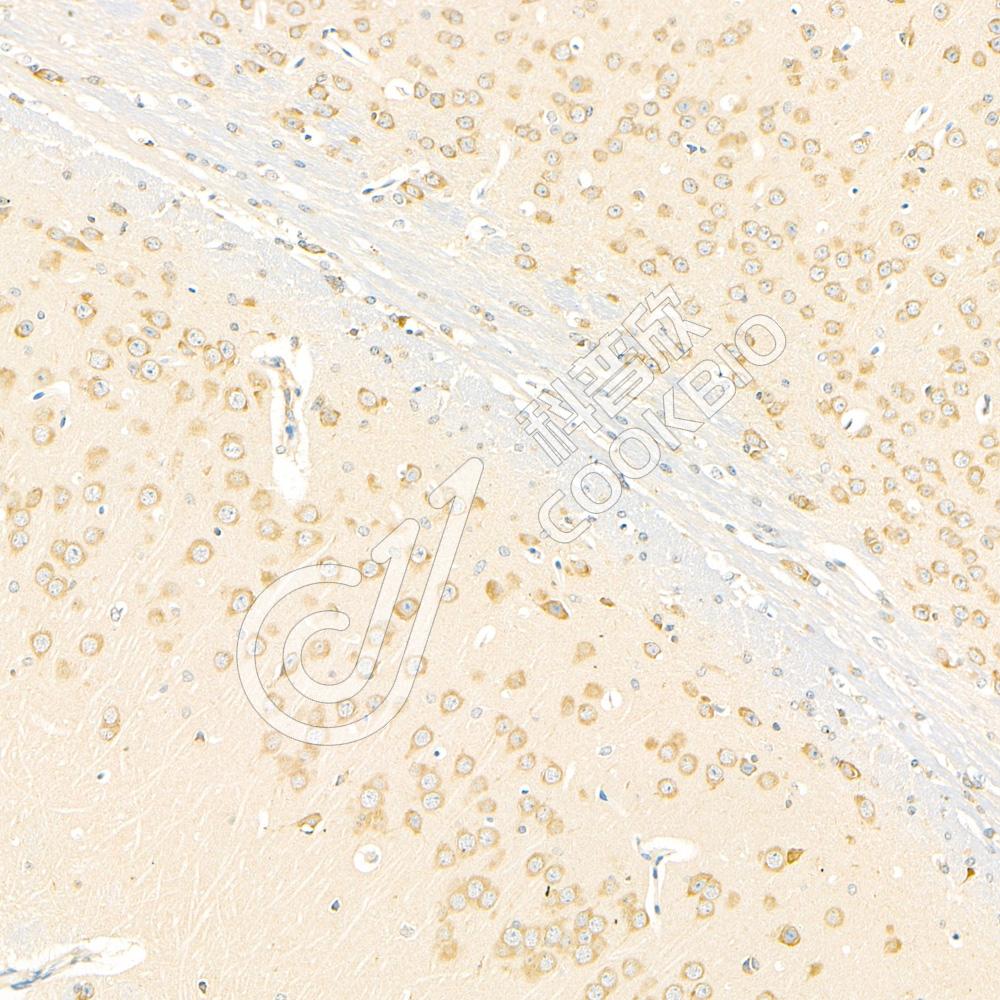

IHC检测Chromogranin A蛋白(货号 K1333948).

样品: 小鼠脑, 4%多聚甲醛 (货号KSG1101) 固定12-24小时.

抗原修复: 柠檬酸抗原修复液(干粉, pH 6.0) (KSG1201), 98℃, 20分钟.

—抗: 1: 2500稀释, 4℃ 孵育过夜.

二抗: S-vision免疫组化多聚二抗(山羊抗兔),即用型 (货号KB3906), 室温孵育20分钟.